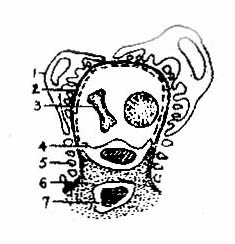

1.微小病变型肾病光镜下肾小球结构基本正常或仅有轻微病变(上皮细胞肿胀、空泡、变性、系膜组织轻度局灶性增生),近端肾小管上皮细胞轻重不等的脂肪变性,所以亦称类脂性肾病。电镜下观察可见肾小球上皮细胞有严重的足突融合现象,故亦称足突型肾病(Foot Process nephrosis)(图4-2-2)。附正常肾小球毛细血管袢模式图(图4-2-1)。

图4-2-1正常肾小球毛细血管袢模式图

1、上皮细胞 2、基底膜 3、红细胞 4.内皮细胞5、足突 6、系膜基质7、系膜细胞

图4-2-2 肾小球微小病变模式图

上皮细胞足突融合